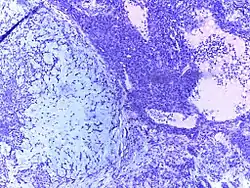

Dysgerminoma | Dysgerminoma characterized by uniform cells resembling primordial germ cells separated by fibrous septa with lymphocytes. | Category: Histopathology of ovarian dysgerminoma | Ovarian dysgerminoma |

![]() |